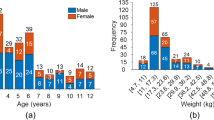

Table 1 summarizes characteristics of the pediatric patient cohort, comprising 40 individuals (13 males, 27 females) with a mean age of 28 months (range: 0.5 to 3.9 years). The cohort included 16 patients with neuroblastoma, 9 with PTLD, 8 patients with sarcoma, 4 with lymphomas and 3 patients with leukaemia.